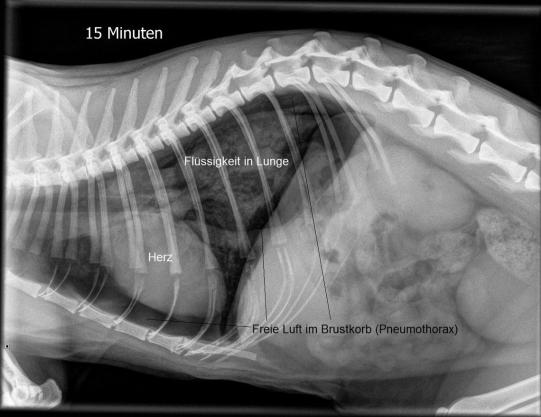

Im Verlauf der nächsten Viertelstunde verbessert sich die Atmung von Muffin leider nicht - im Gegenteil, die Katze atmet noch angestrengter und speichelt stark. In der Zwischenzeit ist der Kater aber schon wieder bei Bewusstsein. Erneut wird ein Lungenröntgen angefertigt - erschreckenderweise zeigt sich nun neben der Flüssigkeitsbildung in der Lunge ein zweites Problem: Muffin zeigt einen Pneumothorax; eine Situation, bei der sich entweder durch ein Riss in der Lunge oder aber einer tiefen Wunde im Brustkorb Luft zwischen der Lunge und dem Brustkorb bildet und so das Lungenvolumen mehr und mehr einschränkt.

Um die Luft zwischen Lunge und Brustkorb zu entfernen, wird bei Muffin umgehend auf beiden Brustseiten eine Brusthöhlenpunktion durchgeführt. Kurz darauf atmet die Katze deutlich besser; ein weiteres Röntgenbild knapp 6 Stunden nach Eintreten des Notfalls zeigt, dass sich der Pneumothorax glücklicherweise nicht erneut verstärkt hat. Auf eine weitere Punktion kann deshalb verzichtet werden.